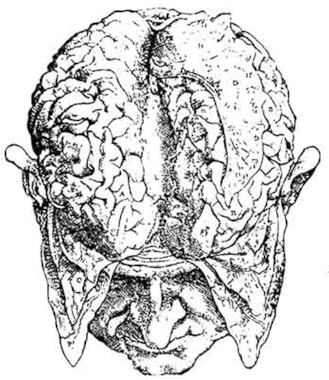

El primer día del año 1861 Broca había asumido el cargo de cirujano en un hospital cercano a París, llamado Bicêtre. El lugar era más un sanatorio o casa de reposo que un hospital, adonde se enviaban (y envían aun hoy) pacientes con enfermedades crónicas, que recibían cuidados durante extensos períodos. En Bicêtre, uno de los pacientes que había atraído la atención de Broca era un hombre llamado Leborgne, que había sido internado más de veinte años antes al perder su capacidad de habla.[74] Los enfermeros lo apodaban “Tan Tan”, porque éstas eran las únicas palabras que podía emitir, aun cuando no había parálisis del conducto articulatorio ni pérdida de la comprensión o la inteligencia. Hacia abril de 1861, el estado de Leborgne se había deteriorado. La muerte era inminente, y Broca pidió se confirmara la condición de Leborgne en cuanto a expresión verbal. Al morir Leborgne el 17 de abril, se efectuó inmediatamente un examen post mortem de su cerebro. Al día siguiente Broca informó a la sociedad que Leborgne había padecido fundamentalmente el deterioro de una porción del lóbulo frontal del hemisferio izquierdo, y que era esa zona del cerebro la responsable de la expresión por medio del lenguaje.[75] Para 1865, se conocían otros varios casos clínicos y exámenes cerebrales parecidos al efectuado con Leborgne, lo bastante coherentes como para ubicar con precisión lo que desde entonces se conoce como zona de Broca, y establecer la importancia de dicha área para un tipo de trastorno del lenguaje, al que Broca denominó afasia.[76] Se trató de un descubrimiento de vastísimas proporciones, que señalaría el comienzo de la edad moderna en nuestra comprensión de las bases físicas del lenguaje. Como corresponde, el cerebro del propio Broca se encuentra preservado hasta el día de hoy en el Laboratorio de Antropología del Museo del Hombre en París.[77]

Interesa advertir que la reciente aplicación de la moderna tecnología de imágenes por CAT-scan es la que ha servido para confirmar las conclusiones anatómicas específicas a las que Broca sólo pudo llegar mediante una inspección visual. En 1984, Jean-Louis Signoret y sus colegas del Hospital Salpêtrière de París realizaron un CAT-scan del cerebro preservado de Leborgne que Broca había estudiado en 1861.[78] El objeto del estudio era rebatir o confirmar una crítica, efectuada en 1908 por el neurólogo Pierre Marie, en el sentido de que era erróneo el juicio de Broca acerca de que el estado del cerebro de Leborgne era resultante de una lesión en la corteza frontal izquierda. Los resultados del CAT-scan indicaron claramente que la lesión estaba precisamente donde Broca había dicho. Marie se había equivocado: Broca tenía razón.